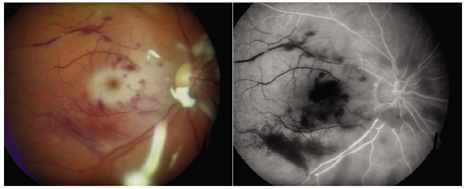

Two adverse events during or after endophthalmitis treatment may markedly influence visual acuity outcomes. Antibiotic toxicity and retinal detachment are significant because further visual loss may occur in spite of successful treatment of the infections. Macular infarction after the use of intraocular aminoglycosides (Fig. 5) is a clinically recognized complication manifesting as a relatively well-defined area of retinal whitening, often in the macula.76,77 Reported cases of macular infarction secondary to administration of intraocular aminoglycosides have been observed after excessive intraocular doses; other cases were reported after apparent injection of a recommended safe dose. A localized increase in the drug concentration in dependent areas of the retina may play a role in aminoglycoside toxicity. If some of the perifoveal capillaries are spared, retention of some central vision is possible.

Fig. 5. Macular infarction following intravitreal amikacin 0.4 mg injection. Left: The color photograph shows whitening of the retinal tissue that involves the macula as well as scattered intraretinal hemorrhages. Right: The angiogram shows prominent capillary nonperfusion that involves the macula. The organism cultured from the vitreous was Staphylococcus epidermidis. Despite resolution of the infection, visual acuity was limited to hand motion only because of the macular infarction.